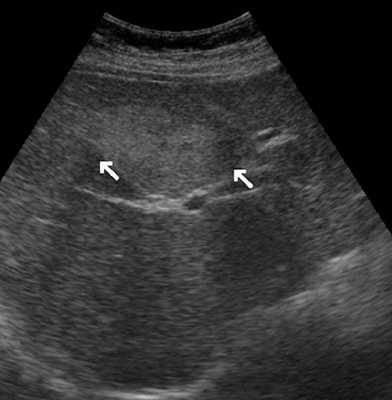

УЗИ брюшной полости. Печень увеличена в размерах, контуры ровные, структура неоднородная, средней эхогенности, признаков портальной и билиарной гипертензии нет. В правой доле печени визуализируется образование размером 142x95 мм, гиперэхогенное, выраженно неоднородное по эхоструктуре, с неровными контурами, наличием мелких эхонегативных зон, имеющее ободок пониженной эхогенности по периферии, с кальцинатами внутри. Образование гиповаскулярное. Желчный пузырь спавшийся. Поджелудочная железа без особенностей. Селезенка нормального размера, структурно не изменена.

Заключение: объемное образование правой доли печени (рис. 1).

а) B-режим. В правой доле печени визуализируется образование размером 142х95 мм, гиперэхогенное, неоднородное по эхоструктуре, с неровными контурами, наличием мелких эхонегативных зон, имеющее гипоэхогенный ободок по периферии.

б) Кальцинаты внутри (стрелки) образования.

Типичными эхографическими признаками капиллярной гемангиомы (рис. 4) являются: небольшой размер (от 20 до 40 мм) образования, однородные, гомогенные гиперэхогенные, с четкими ровными (иногда неровными волнистыми, бугристыми в виде "штрихов") контурами, имеющие вид "спущенного шара"; хорошо отграничены от окружающей ткани; без затухания, иногда с усилением эхосигнала позади образования [1, 5, 12-14]. Типичные эхографические признаки кавернозной гемангиомы: образования больших размеров, с четкими бугристыми контурами; хорошей очерченностью от окружающей их неизмененной ткани печени; характеризуются высокой эхогенностью и неоднородностью структуры, которая обусловлена наличием кавернозных полостей, определяемых при УЗИ в виде эхонегативных зон различных форм и размеров [5, 9, 12]. При цветовом допплеровском картировании (ЦДК) кровоток в самой гемангиоме в 86,9% случаев, как правило, не определяется (образование аваскулярное или гиповаскулярное); в 75% случаев хорошо виден подходящий к гемангиоме питающий сосуд с признаками артериального, ламинарного кровотока. При оценке количественных показателей кровотока в артериях средняя систолическая линейная скорость кровотока, по данным разных исследователей, в гемангиомах составляет от 37,56±17,68 до 15,0±16,0 см/с; линейная скорость венозного кровотока в среднем достигает 20,61±9,8 см/с; PI в гемангиоме в среднем равен 0,91±0,14, RI - 0,5 [1, 5, 13-17]. Индекс допплеровской перфузии при гемангиомах - 0,22, что значительно меньше, чем при злокачественных образованиях (0,62±0,1) [1].

а) В-режим. В печени визуализируется образование небольшого диаметра, однородное, гомогенное гиперэхогенное, с четкими ровными контурами, хорошо отграниченное от окружающей ткани, с усилением эхосигнала позади образования (стрелки).